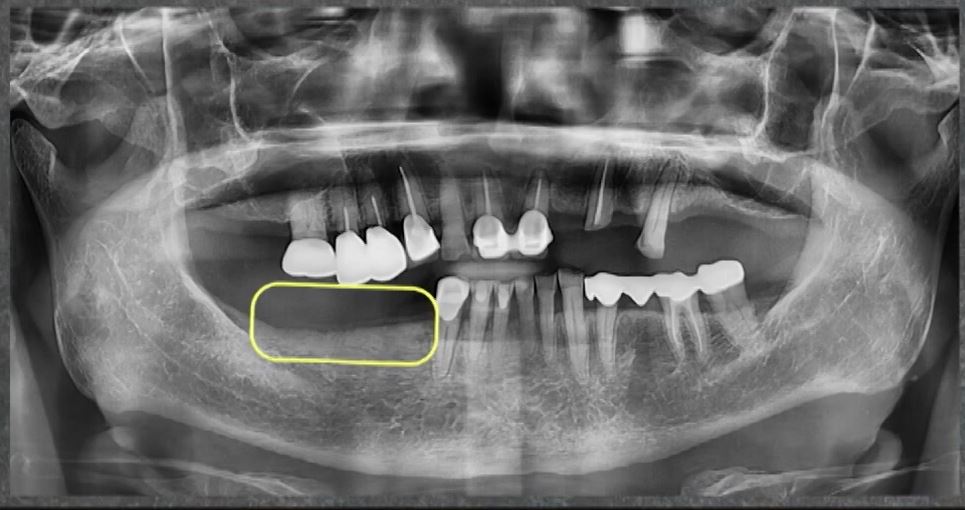

사진에 보이는 네모칸 부위에

3개의 임플란트를

무절개로 식립할 예정입니다.

타치과에서 뼈이식 진단을 받고

하루플란트치과를 찾아주신 분인데요.

사진으로 보시다시피

잇몸뼈의 폭이 매우 좁은 상태입니다.